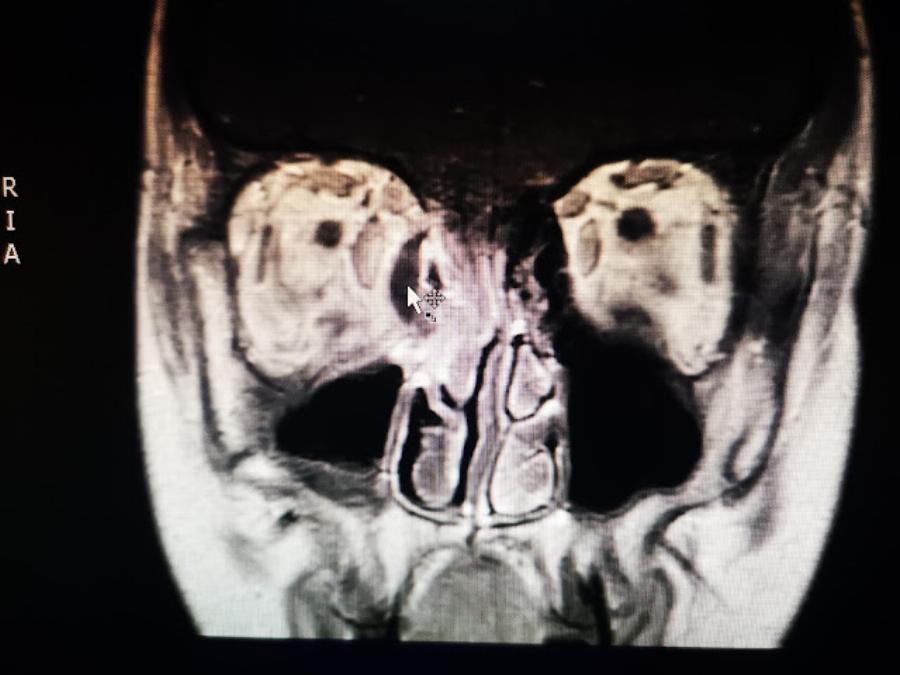

Από την ΩΡΛ κλινική του ΠΓΝΙ πραγματοποιήθηκε χθες βράδυ για πρώτη φορά επείγουσα χειρουργική επέμβαση διάνοιξης και παροχέτευσης αποστήματος της οφθαλμικής κοιλότητας με ενδοσκοπική τεχνική διαμέσου της μύτης χωρίς εξωτερικές τομές στο πρόσωπο αναφέρει το epirus-tv-news.gr

Το απόστημα της οφθαλμικής κοιλότητας (υποπεριοστικό απόστημα) είναι μια επείγουσα και ιδιαίτερα επικίνδυνη επιπλοκή μετά από οξεία φλεγμονή των παραρρινίων κόλπων (παραρρινοκολπίτιδα) η οποία μπορεί να οδηγήσει μέσα σε λίγες ώρες σε μόνιμες βλάβες του οφθαλμού και χρειάζεται επείγουσα χειρουργική αντιμετώπιση.

Οι ενδοσκοπικές επεμβάσεις των παραρρινίων κόλπων είναι ελάχιστα τραυματικές για τον ασθενή μια και αποφεύγονται οι εξωτερικές τομές, είναι όμως δύσκολες λόγω της πολύπλοκης ανατομίας της περιοχής οποία είναι ξεχωριστή στον κάθε ασθενή, και των ιδιαίτερα σημαντικών δομών που βρίσκονται πολύ κοντά (μάτια, εγκέφαλος). Συγκεκριμένα σε ασθενείς με κορονοϊό η συγκεκριμένη επέμβαση θεωρείται υψηλού κινδύνου για την επιμόλυνση του προσωπικού, λόγω παραγωγής αερολύματος.